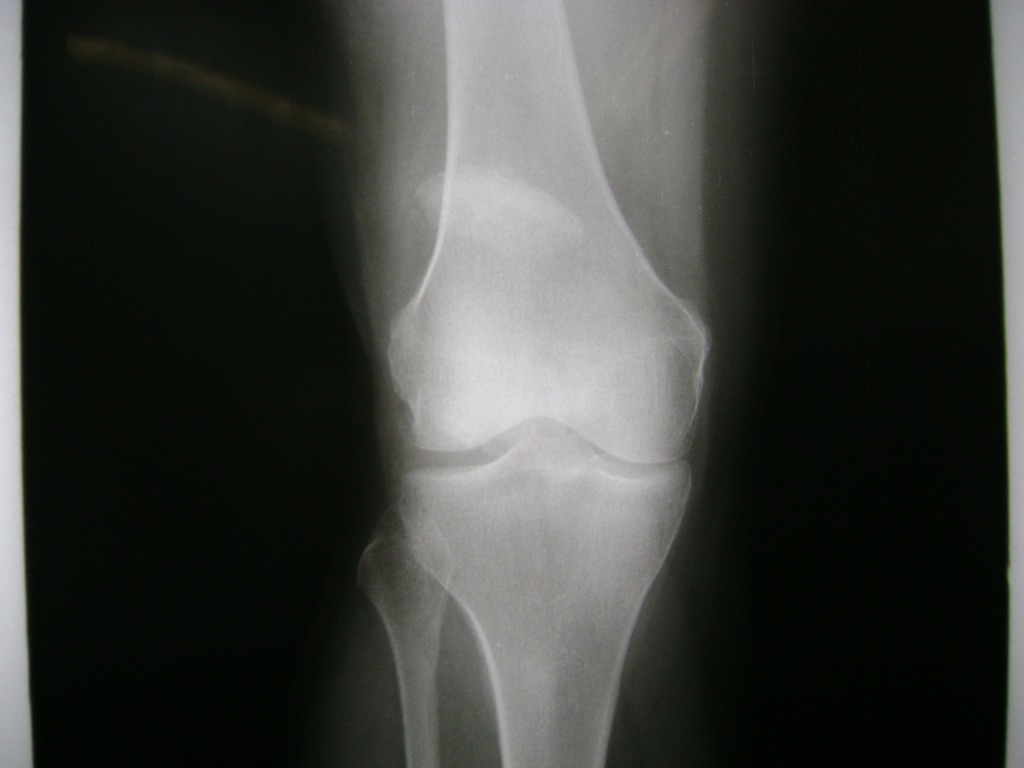

Cirugía de Rodillas